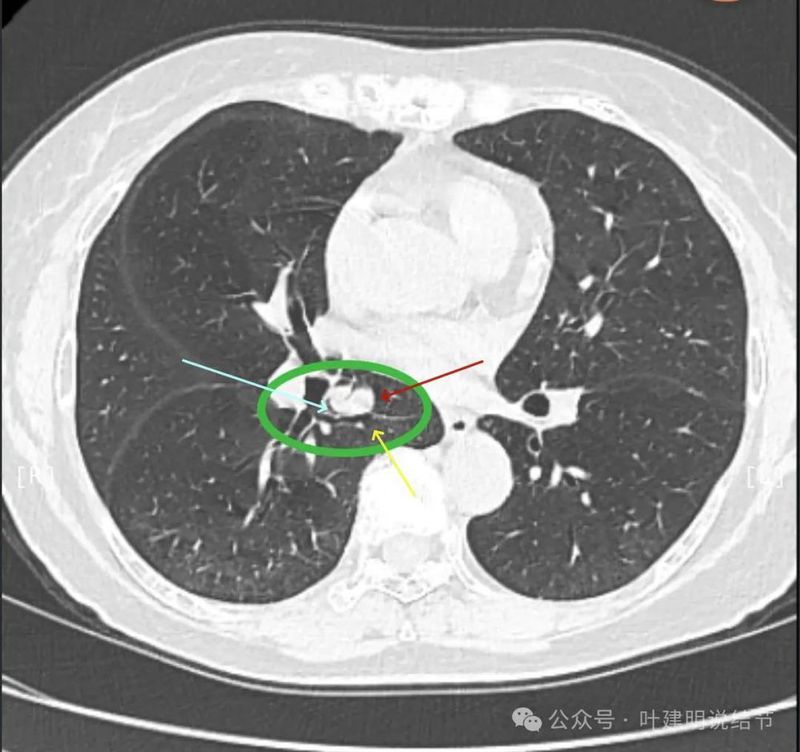

天蓝色箭头示病灶与支气管之间有缝隙,但贴的较近;黄色箭头示支气管管腔;红色箭头示病灶,边缘光滑。

支气管受压,但无明显破坏;与支气管之间紧贴位有的位置仍有缝隙;病灶边缘光滑。

病灶密度较为均匀,对支气管是压迫后移位。表面光滑。

天蓝色箭头所指处是北段支气管与病灶之间,感觉较2月份贴得近了一点点。病灶表面仍是光滑的,总体感觉有膨胀性。